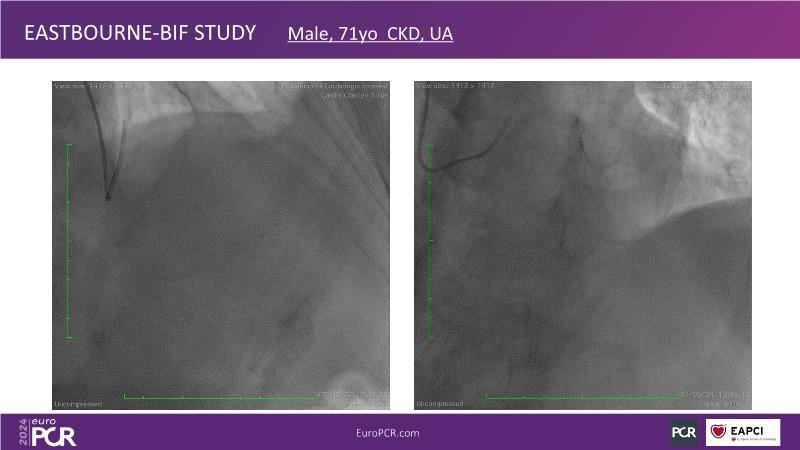

Browse this EuroPCR 2024 session to explore the safety and efficacy of sirolimus-coated balloons from pre-clinical data, review MagicTouch data from real-world populations with case-based examples, and learn about the MagicTouch sirolimus-coated balloon clinical programs. Discover insights and takeaways from the significance of the EASTBOURNE subgroups, and analyze the challenges and opportunities in PCI for diabetic patients.